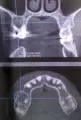

При осмотре у врача в прошлом году, у меня обнаружили кисту на верхнем зубе под металлической коронкой. Коронка установлена на штифте, от зуба практически ничего не осталось. Полтора месяца назад я сильно заболела, и десна очень сильно опухла над этим зубом, болел зуб, но через 3 дня боль спала.

Сделала панорамный снимок и в сравнений с прошлым годом киста увеличилась в размере. Врач сказал, что есть несколько вариантов:

Прикрепленые фото